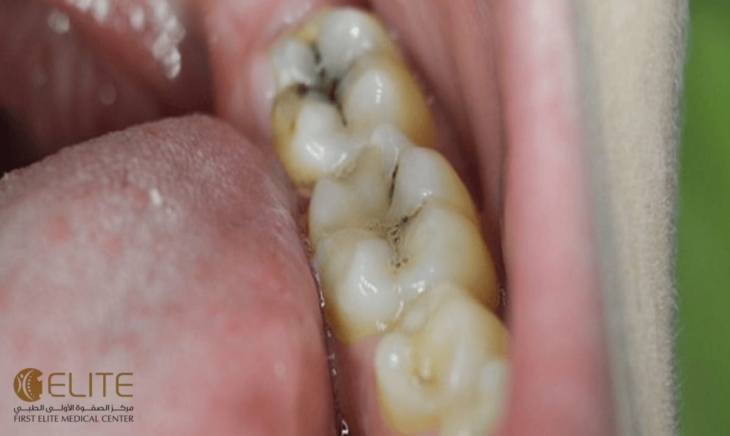

السكريات جزء لا يتجزأ من النظام الغذائي اليومي، لكنها تُعد من أبرز العوامل التي تُهدد صحة الأسنان. فالاستهلاك المفرط للسكريات، خاصةً في غياب العناية الفموية الجيدة، يؤدي إلى سلسلة من التفاعلات البيولوجية التي تُضعف الأسنان وتُعرضها للتسوس وأمراض اللثة.

عند تناول السكريات، تتفاعل مع البكتيريا الموجودة طبيعيًا في الفم، خاصةً تلك التي تُعرف باسم Streptococcus mutans. هذه البكتيريا تستخدم السكريات لإنتاج أحماض، وهذه الأحماض تبدأ في مهاجمة طبقة المينا (الطبقة الخارجية الصلبة للأسنان).

دورة التسوس

1. تناول السكريات (مثل الحلويات، المشروبات الغازية، العصائر الصناعية).

2. تغذية البكتيريا على هذه السكريات.

3. إنتاج الأحماض التي تُهاجم المينا.

4. تآكل المينا وظهور ثقوب صغيرة.

5. تطور التسوس ليصل إلى طبقات أعمق من السن.

السكريات ليست العدو الوحيد للأسنان، لكن تأثيرها المباشر في تغذية البكتيريا وإنتاج الأحماض يجعلها من أخطر العوامل المسببة للتسوس. التوازن بين النظام الغذائي والعناية الفموية هو المفتاح للحفاظ على ابتسامة صحية تدوم مدى الحياة.